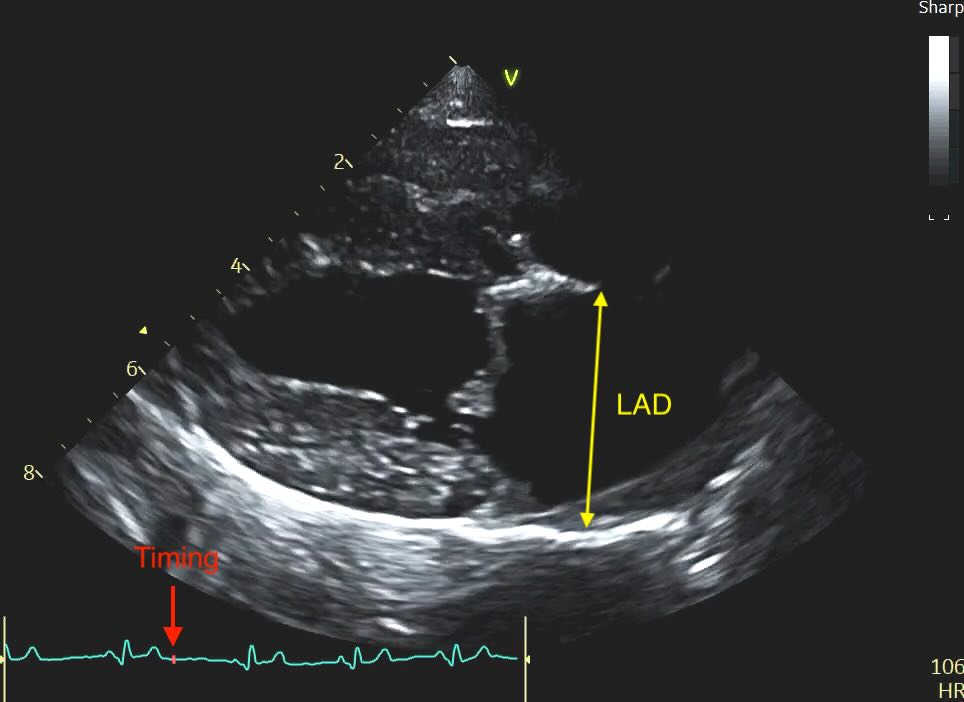

Unlike the LA:Ao, which we time to early diastole, the LAD is measured at end-systole. This is when the left atrium is at its maximal volume, having just finished filling from the pulmonary veins.

- The Timing: Select the frame just before the mitral valve opens (or 1-2 frames after the peak of the T-wave if using an ECG). This is easy with practice, scroll backwards in your loop until you have a closed valve, then step forward frame by frame until it pops open, and go back again 1 frame.

Caliper Placement:

Measure the distance from the inner wall (endocardial border) of the middle of the interatrial septum to the inner wall of the posterior free wall.

The line must be at the widest point of the atrium and must remain parallel to the mitral valve annulus.